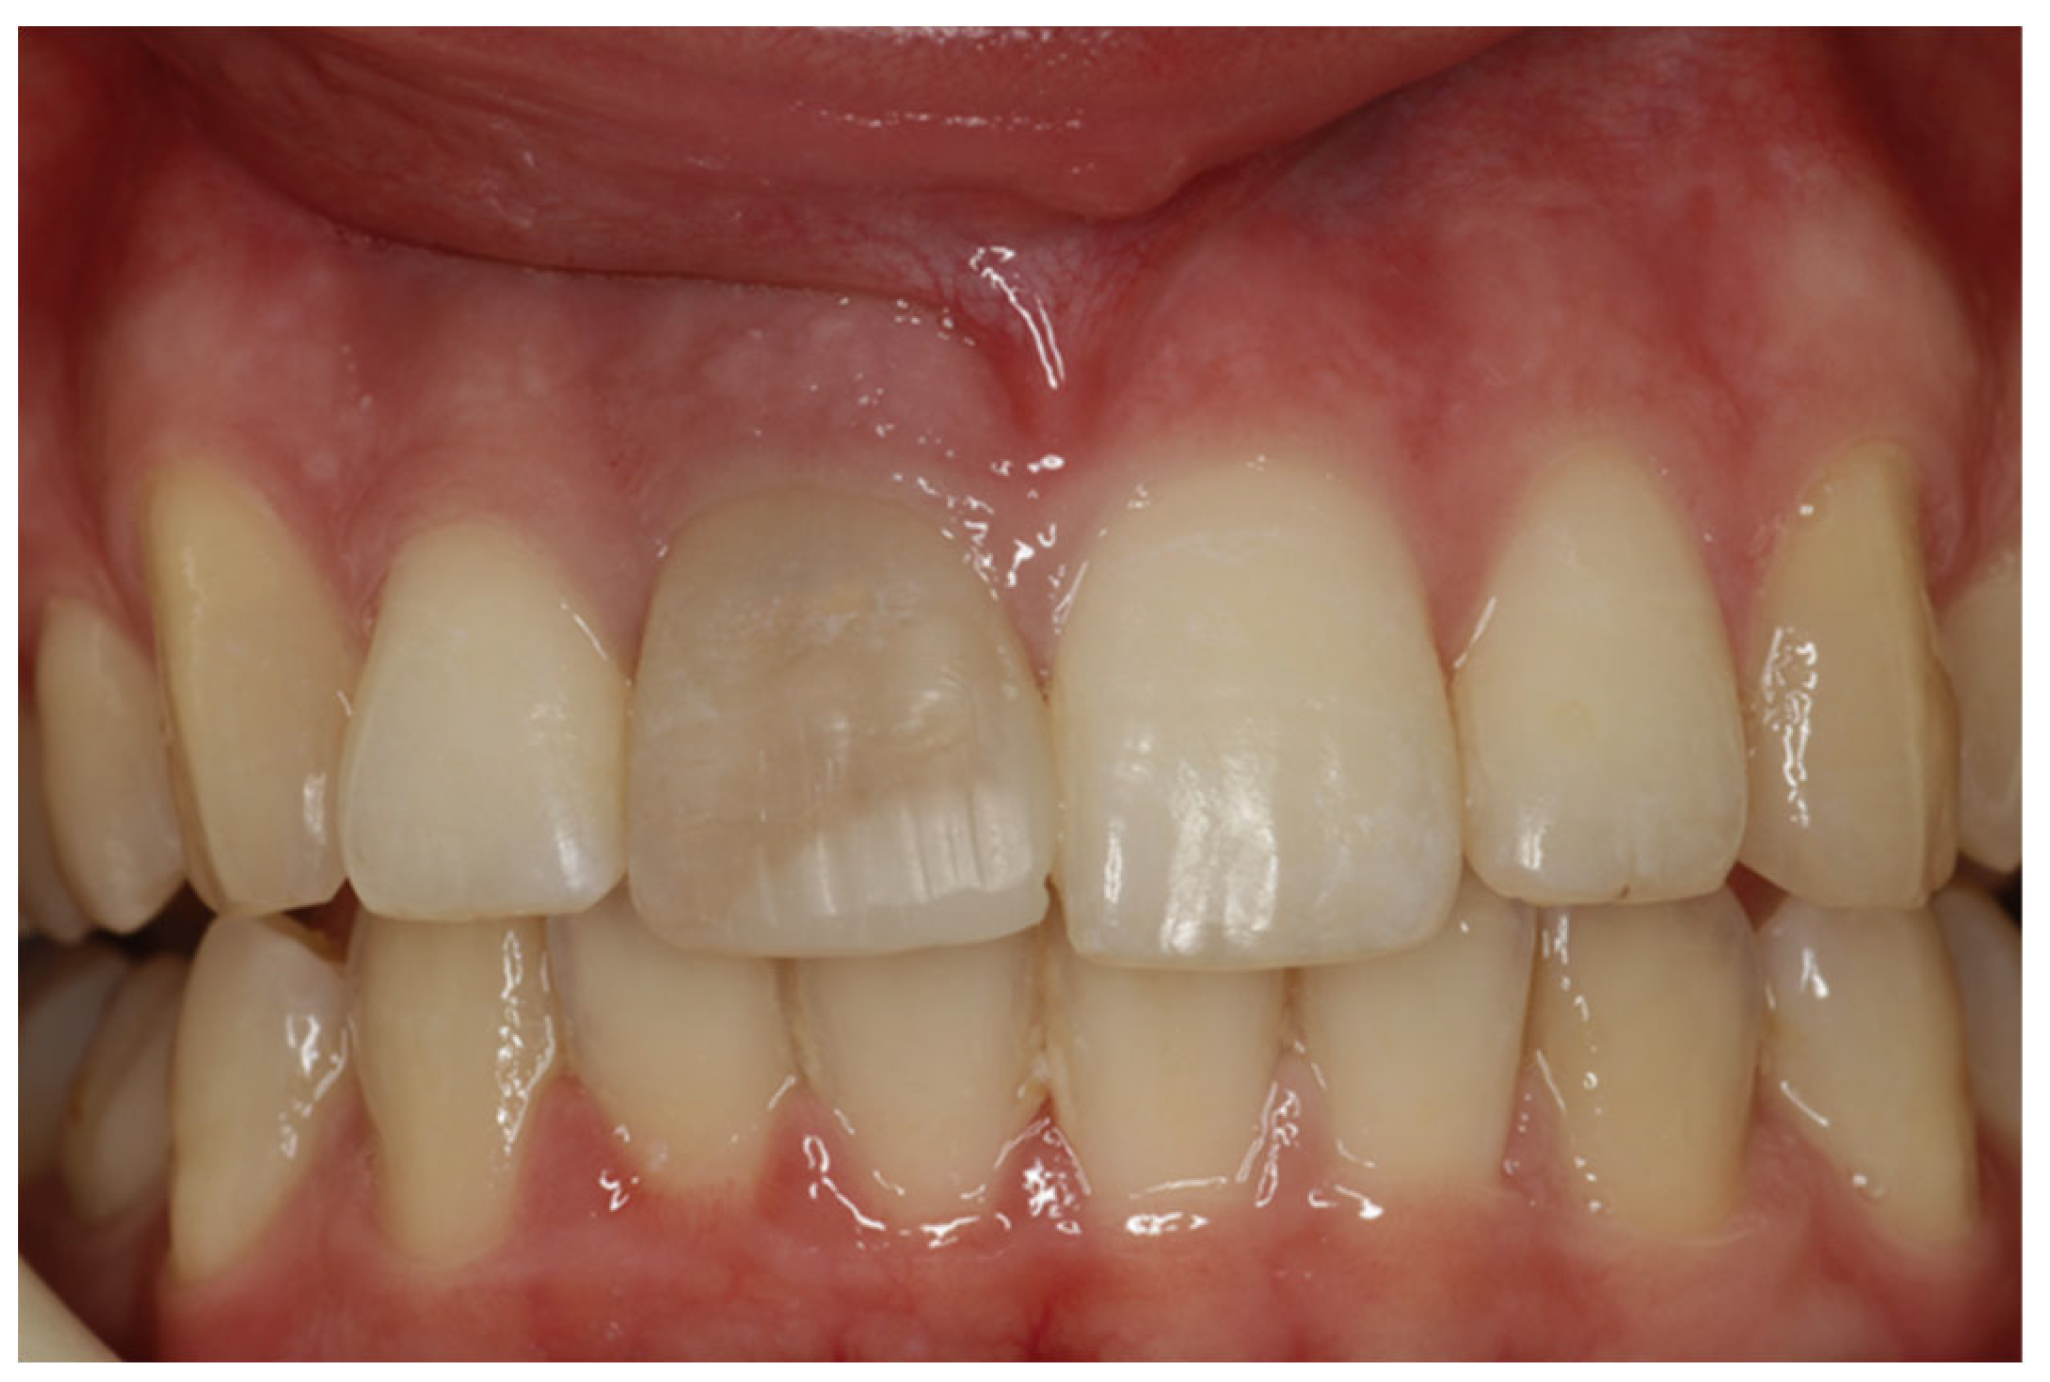

2. Clinical Case

- Porcelain veneers provide a reliable and conservative procedure for the aesthetic restoration of endodontically treated teeth that have undergone discoloration.

- For better aesthetic results, in cases of intrinsic discoloration, an internal tooth bleaching procedure may precede.

- Considering bonding and cementation, adhesively cemented high translucency monolithic zirconia seems to be a suitable option for veneers.